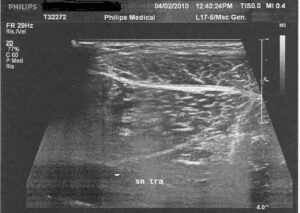

Prima immagine ecografica 04/03/2010

L’ecografia del polpaccio mediale destro, zona dolorante, mostra una piccola area ipoecogena accanto al muscolo, estesa per circa 8 mm, nella parte interna, forse dovuta ad una lesione muscolare locale. Inoltre, è possibile vedere una leggera area ipoecogena posta nella zona inferiore del muscolo, vicino alla fascia muscolare, forse sangue fluido.

UItima immagine ecografica 02/04/2010

C’è ancora una piccola area ipoecogena del polpaccio mediale sinistro, grande circa 2 mm, che mostra anche un consolidamento delle fibre, senza apprezzabile falda liquida intra o peri lesionale.